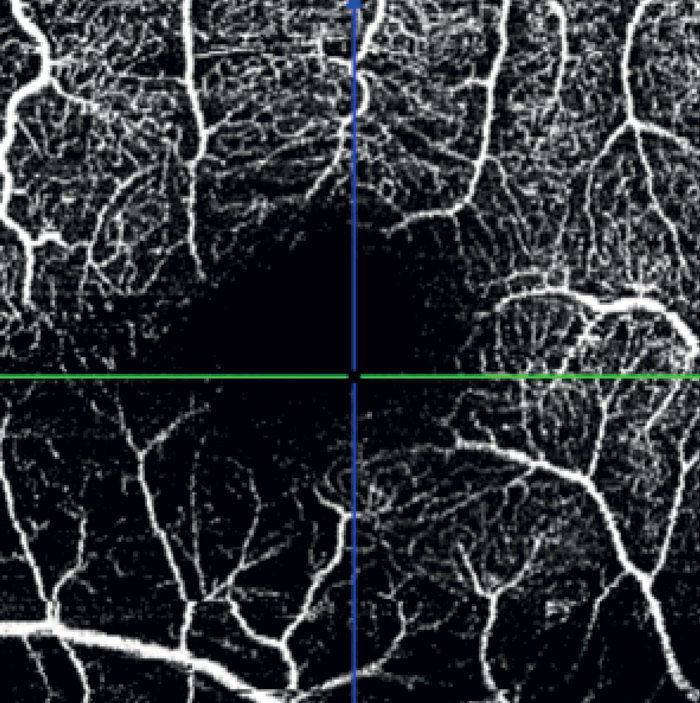

A wedge-shaped defect and inferotemporal thinning of the RNFL in the right eye corresponded with OCTA of inferotemporal capillary dropout (see Figure 6). OCTA of the Macula revealed diffuse capillary dropout inferiorly consistent with retinal thinning (see Figure 7). These dramatic images matched the paracentral visual field deficit in the right eye.